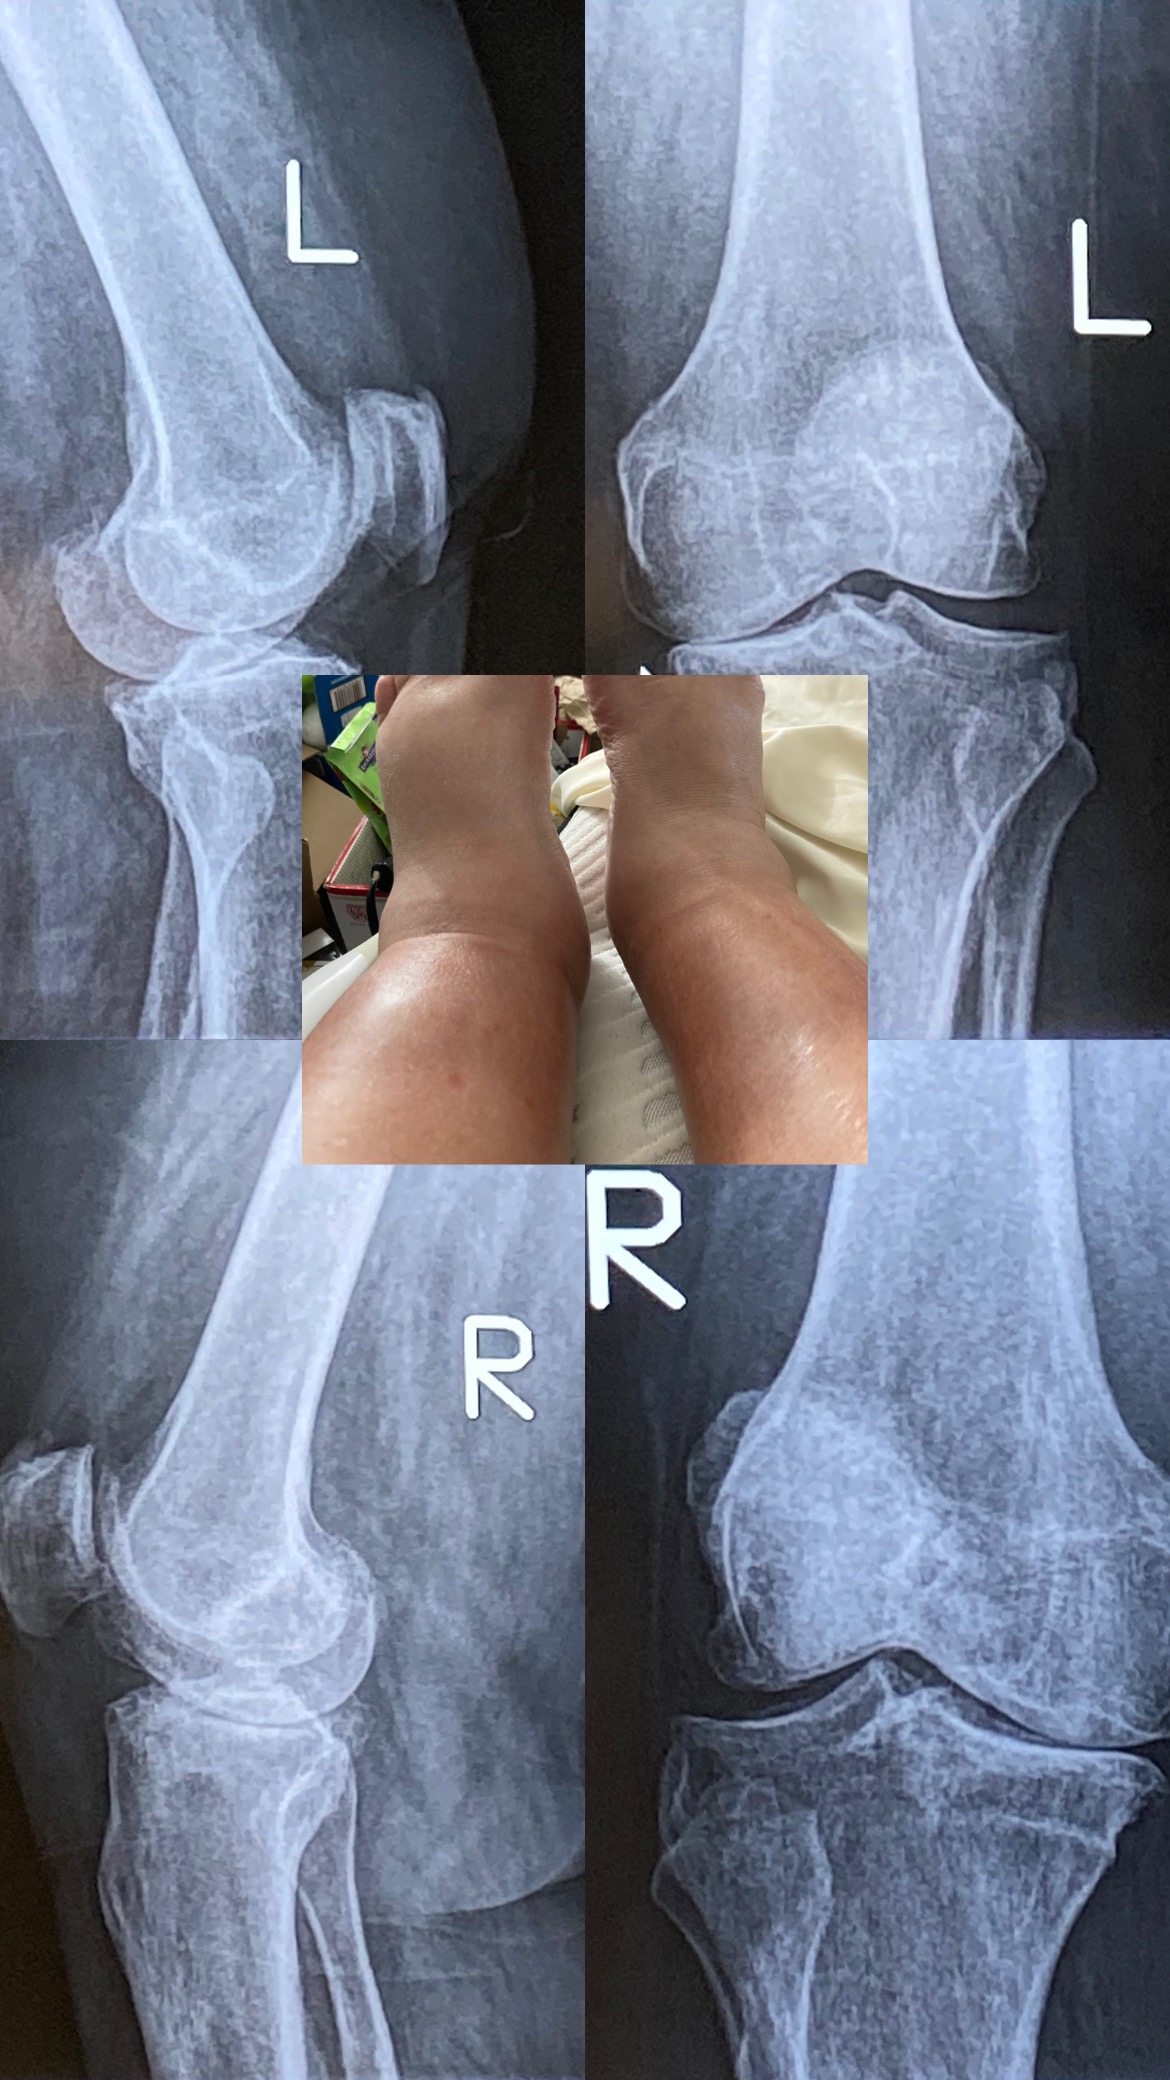

Right now, I need two knee replacements – but because of my medical condition, traditional surgery isn’t safe for me. I have been living with Chronic Cellulitis and Lymphedema since 1999, after giving birth. Lymphedema is a rare condition (1 in 1000 people) that causes my lymphatic system to not drain properly, leaving me vulnerable to serious infections from even the smallest cut, scratch, or bite. I've been in and out of the hospital countless of times to count due to this.

The pain in my knees is constant. I’m bone-on-bone in my left inner knee and right outer knee. It’s getting worse every single day. Walking is becoming nearly impossible, and without help, I’ll end up in a wheelchair permanently.